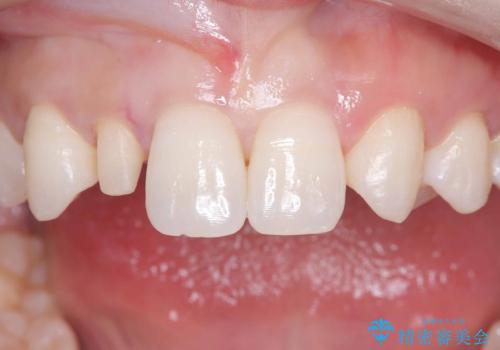

- 「前歯の見た目が気になる」を主訴に来院された患者様です。

右上2が矮小歯だったので、オールセラミッククラウンで審美修復しました。

- 税込165,000円(オールセラミッククラウンスペシャル154,000円+仮歯11,000円)費用は治療当時の料金となります